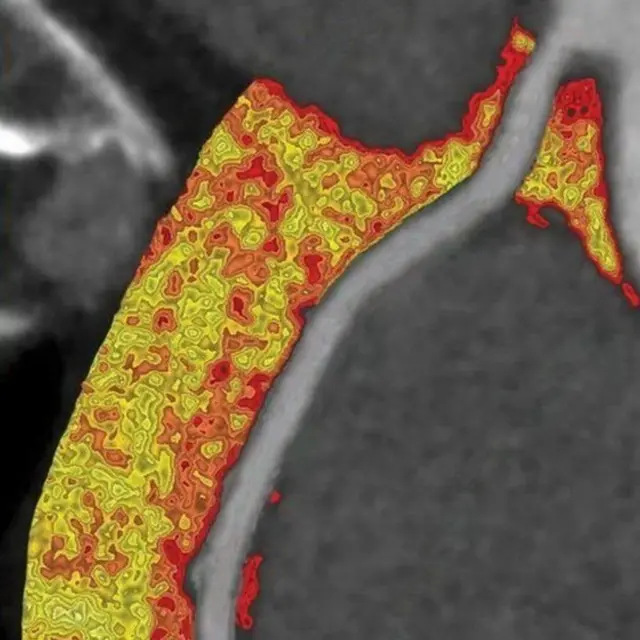

सीटी स्कोअरवरूनही फुफ्फुसांमध्ये विषाणू संसर्ग किती पसरला आहे, याचा अंदाज बांधता येतो, असं बीएलके मॅक्स हॉस्पिटलचे वरिष्ठ संचालक डॉ. संदीप नायर सांगतात. कोरोना संसर्ग झाल्यानंतर 7 दिवसांनंतरच सीटी करण्याचा सल्ला ते देतात.

फोटो स्रोत, SPL

हा स्कोअर 10/25 पेक्षा जास्त असेल तर तुमच्या फुफ्फुसात मध्यम स्वरुपातील संसर्ग आहे. हा स्कोअर 15/25 पेक्षा जास्त असेल डॉक्टर हॉस्पिटलमध्ये जाण्याचा सल्ला देऊ शकतात.